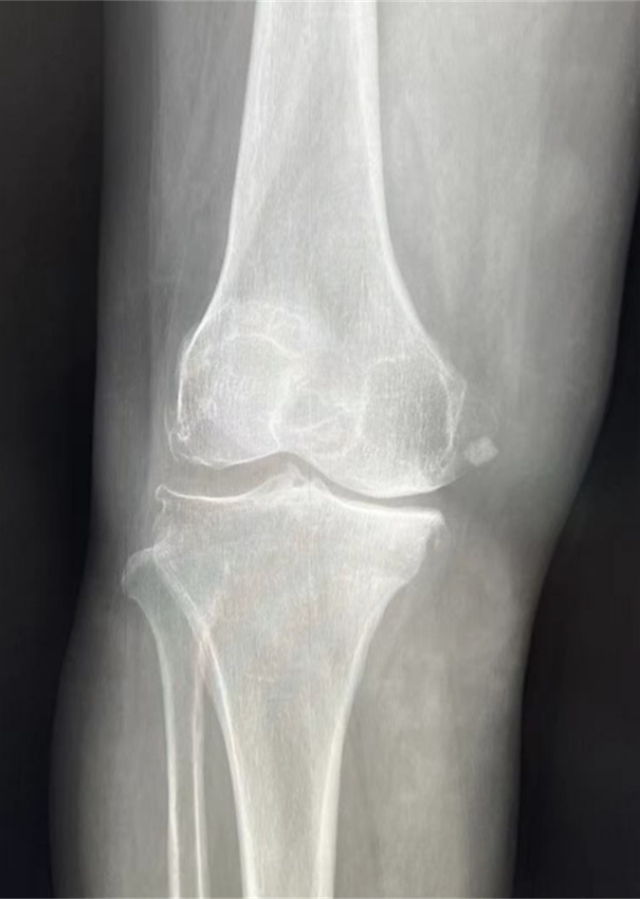

患者术前影像资料